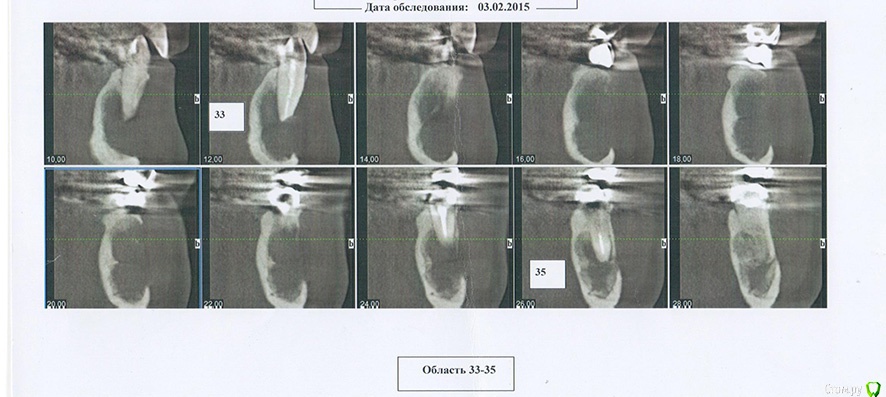

Helenka Опубликовано 29 февраля, 2016 Поделиться Опубликовано 29 февраля, 2016 Здравствуйте! В октябре 2014 года была сделана операция по удалению кисты нижней челюсти. Операцию делали в Москве. Я сама из Волгограда. У меня есть снимки после операции сделанные в феврале 2015 года.И снимки в феврале 2016 года.Видно, что идет формирование кости. В связи с тем, что до Москвы доехать никак не получается, а местные стоматологи как-то жмут плечами, может что посоветуете? У меня вопрос: перед передними зубами нижней челюсти нет на данный момент кости. Она нарастет со временем или надо провести какую-нибудь дополнительную операцию. И те темпы с которыми у меня увеличивается толщина кости - это нормальная скорость или слишком медленно? Ссылка на комментарий